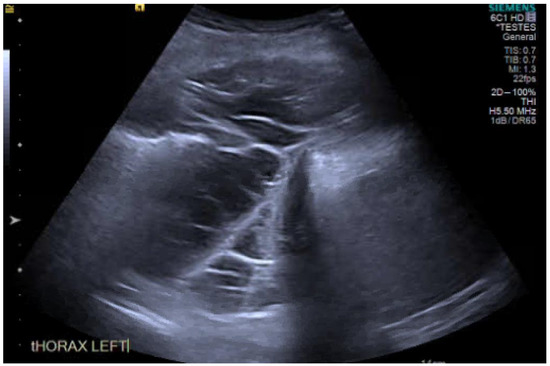

13. Ultrasound